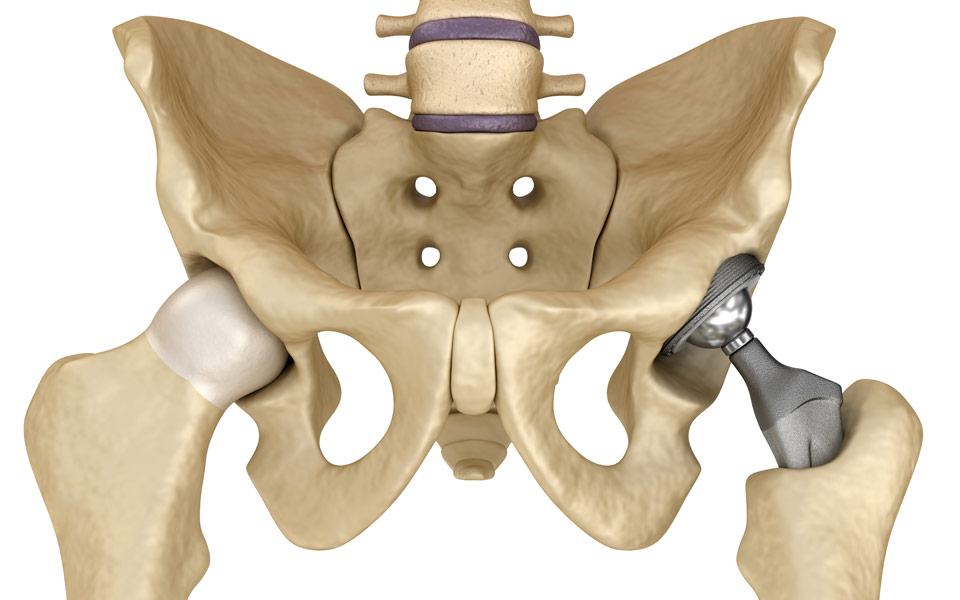

Ολική Αρθροπλαστική Ισχίου-Γόνατος με Προσπελάσεις Ελάχιστης Επεμβατικότητας

Οι αρθρώσεις του ισχίου και του γόνατος είναι οι μεγαλύτερες αρθρώσεις του ανθρωπίνου σώματος. Σκοπό έχουν τη μεταφορά του σώματος προς διάφορες κατευθύνσεις και τη στήριξη του κορμού. Επειδή είναι έντονα φορτιζόμενες αρθρώσεις, υπόκεινται σε μηχανική καταπόνηση και φθορά.

Νέα Αρθροπλαστική Ισχίου με κοχλιωτά εμφυτεύματα τιτανίου αντίστοιχα αυτών της γνάθου

Τα νέα κοχλιωτά εμφυτεύματα τιτανίου, τόσο στη γνάθο όσο και στην κοτύλη, λύνουν οριστικά το θέμα των εμφυτευμάτων σε αυτές τις δύσκολες και υπερβολικά φορτιζόμενες οστικές περιοχές.

Αναθεώρηση της ολικής αρθροπλαστικής του ισχίου: Τώρα και με τεχνική ελάχιστης επεμβατικότητας ASI

Η ολική αρθροπλαστική ισχίου είναι μία από τις πιο επιτυχημένες χειρουργικές επεμβάσεις στην ορθοπαιδική. Παρόλα αυτά, ένας σημαντικός αριθμός ασθενών υποβάλλεται σε αναθεώρηση (δεύτερη επέμβαση/επανεπέμβαση/revision).